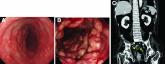

ArticleWhat's your diagnosis?Author:Dong Hoon BaekPublish date: April 29, 2022A 60-year-old man with C3 tetraplegia was referred to our department for evaluation of abdominal pain and hematochezia.Read More